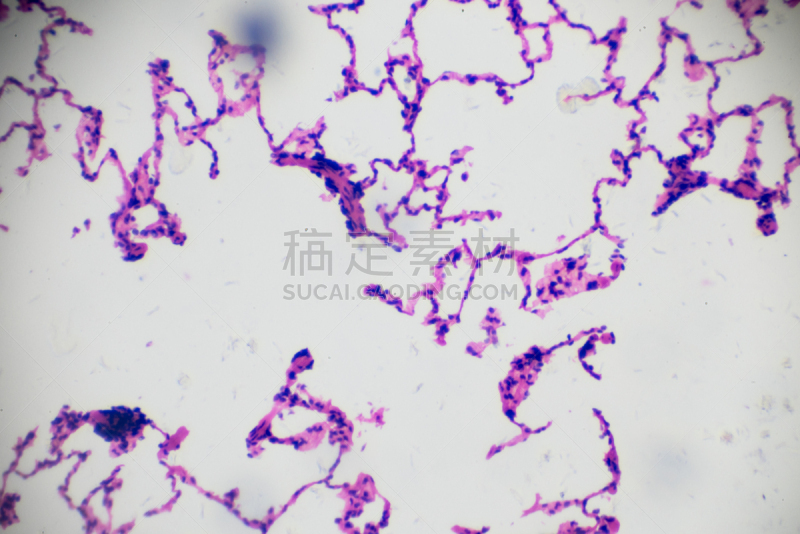

显微镜下的小鼠肾脏详情